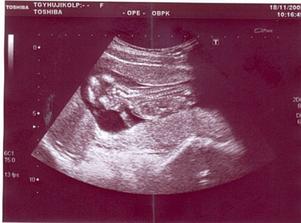

*18.11.2009 ... UTZ v 15+0tt a odběry na triply

*20.11.2009 ... 15+2tt, první výraznější pohyby🙂